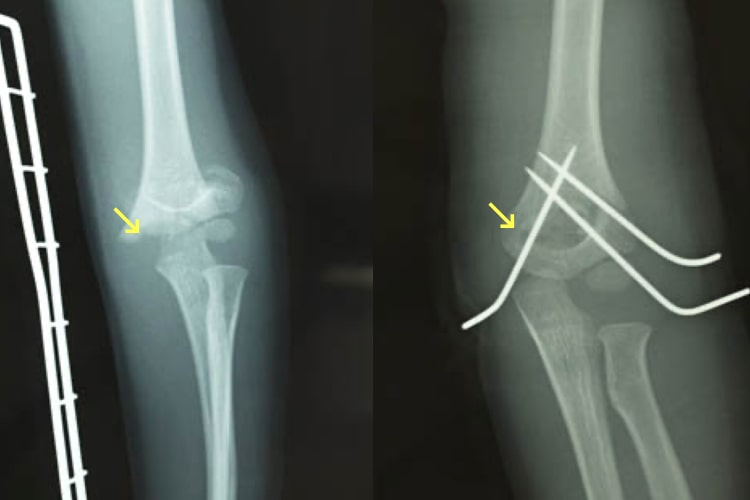

小児上腕骨顆上骨折

上腕骨顆上骨折写真

上腕骨顆上骨折

小児の場合は転倒することで容易に肘周囲の骨折を起こすことがあります。その中でも上腕骨顆上骨折は最も頻度が高く、肘の変形を起こすこともあり注意が必要です。骨折のずれが小さい場合はギプスで固定するのみで骨もつきます。しかし大きくずれてしまっている場合は肘の変形や神経麻痺、血行障害の危険性もあり、手術治療が必要となります。